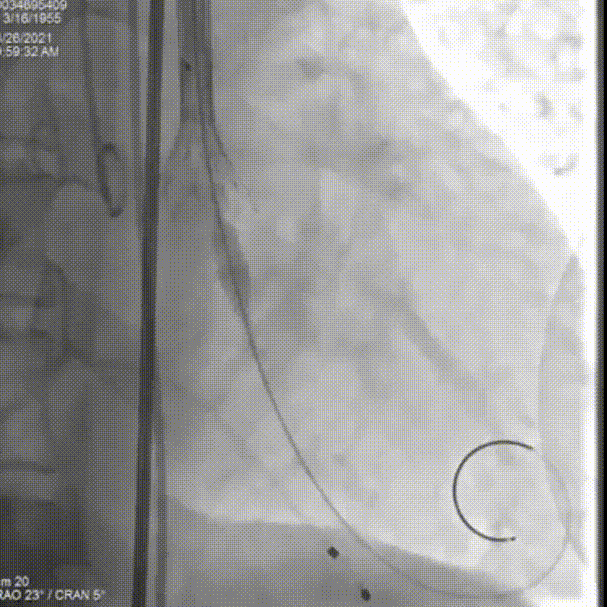

人工瓣有相应折叠,全部回收撤出体外

更换后瓣膜再一次进行释放

部分回收进行位置的微调整

完全释放后,主动脉根部造影